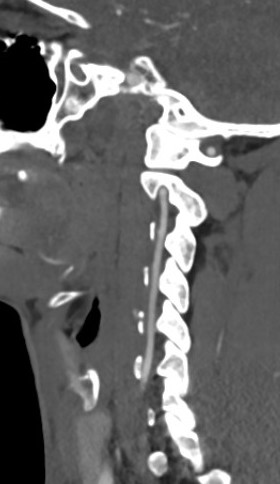

3 Fascial layers

1. Deep cervical fascia

- under the subcutaneous fat

- invests neck like collar

- clavicle / sternum / spine scapula - mandible / base of skull

- invests sternocleidomastoid (SCM) & trapezius

- have to incise so can retract SCM

- platysma and external jugular vein superficial to deep cervical fascia

2. Pretracheal fascia

- anterior neck only

- covers thyroid / tracheal / oesophagus

- deep to the strap muscles

- extends from hyoid into chest

- fuses laterally with carotid sheath

- have to divide to retract carotid sheath laterally

3. Prevertebral fascia

- base of skull to T3

- invests longus colli and sympathetics

- covers ALL

- divide to separate longus colli muscles to approach vertebral bodies and discs